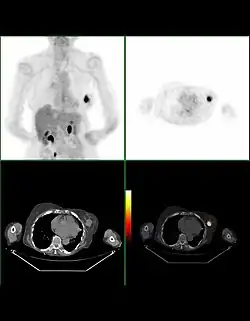

Bilan d'extension

La recherche de métastases est fondamentale dans la stratégie du traitement du cancer du sein. Mais, malgré les nombreuses études réalisées ou la connaissance approfondie de certaines explorations, il n'existe actuellement aucune stratégie validée de recherche systématique de métastase dans le cancer du sein.

La plupart des recommandations proposent actuellement un bilan d'extension comportant un examen clinique soigneux à la recherche de métastases ganglionnaires, une radiographie thoracique, une échographie hépatique et une scintigraphie osseuse. Pour les tumeurs de très petite taille, ce bilan peut être facultatif.

En revanche, pour les tumeurs évoluées (tumeurs inflammatoires, multifocales, envahissement ganglionnaire important), le risque métastatique initial est élevé et peut justifier un bilan plus poussé comportant une tomodensitométrie corps entier et une IRM mammaire.